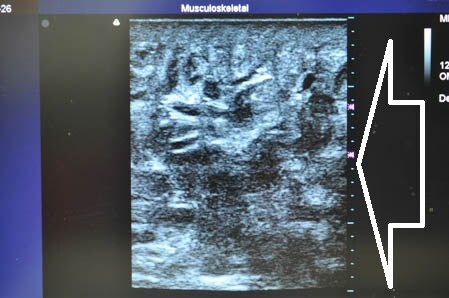

いつものように3Dタッチビューから。

白い矢印部分が皮下脂肪層です。

右の太もも後面です。